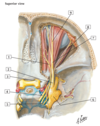

1 - stylohyoid muscle

1 - Digastric muscle

1 - trochlear nerve (IV)

2 - ophthalmic nerve (V1)

3 - optic nerve (ii)

4 - oculomotor nerve (iii)

5 - abducent nerve (VI)

6 - trigeminal (semilunar) ganglion

7 - frontal nerve

8 - lacrimal nerve

9 - supra-orbital nerve